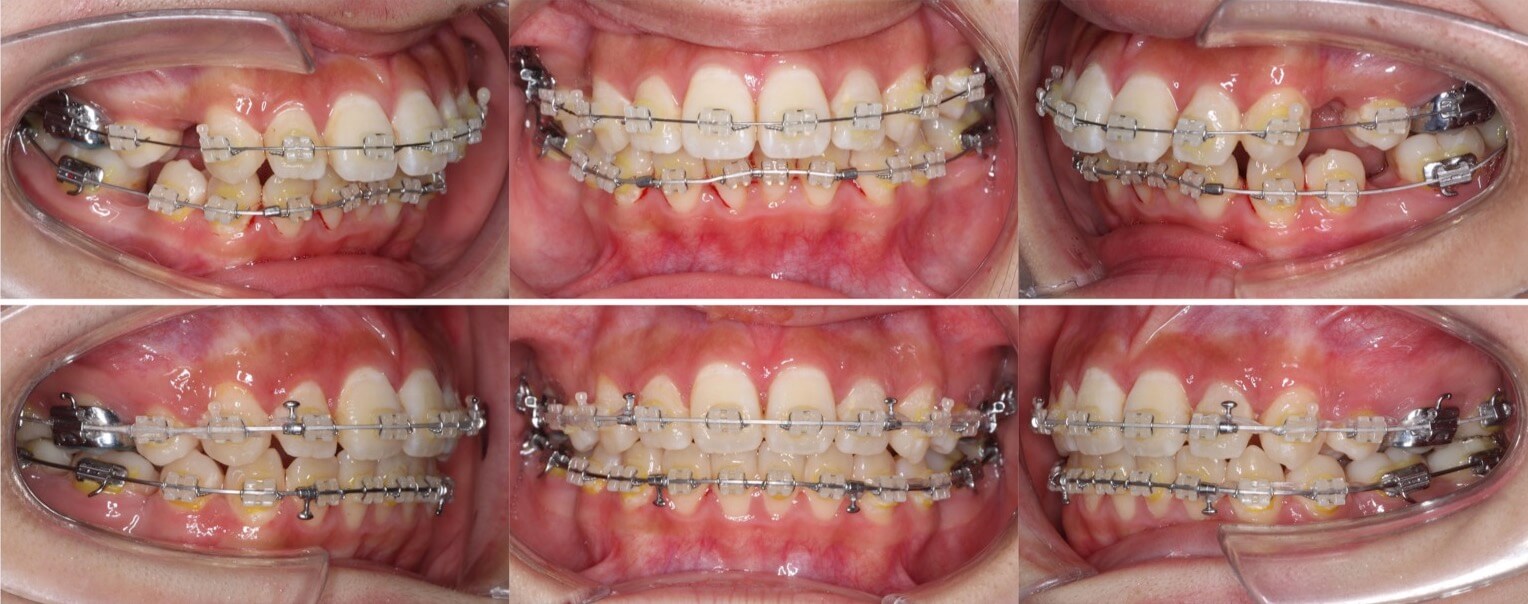

「開咬ならマウスピースも可能」

20代女性・マウスピース型装置・前歯傾斜型

マウスピース型矯正治療は前歯の歯根の後方移動が難しく、口ゴボ症例の適応症は少ないと言えます。その中で、開咬症例は数少ない適応症です。外開きになっている前歯を傾斜移動をコントロールしながら、後方移動させました。

<治療シミュレーション>

慎重に犬歯と前歯を後方移動させる。奥歯の多少の前方移動は許容できるため、小さめのアタッチメントを設置。

※マウスピース型カスタムメイド矯正歯科装置は完成物薬機法対象外の矯正装置であり、医薬品副作用被害救済制度の対象とはならない可能性があります。

<症例概要> 難易度:★★★★☆

主訴:口元の突出と前歯のかみ合わせ

年齢・性別:20代女性

住まい:千葉県八千代市

症状:開咬・上下顎前歯唇側傾斜・叢生

治療方針:抜歯空隙の閉鎖(中等度固定)

治療装置:マウスピース型矯正装置(アライナー装置)

抜歯:上下左右4番(計4本)

治療期間:2年1か月

アライナー枚数:29+27+20ステージ

リテーナー:上下クリアタイプ+フィックスタイプ

治療費用:990,000(税込)

代表的副作用:痛み・治療後の後戻り・歯根吸収・歯髄壊死・歯肉退縮